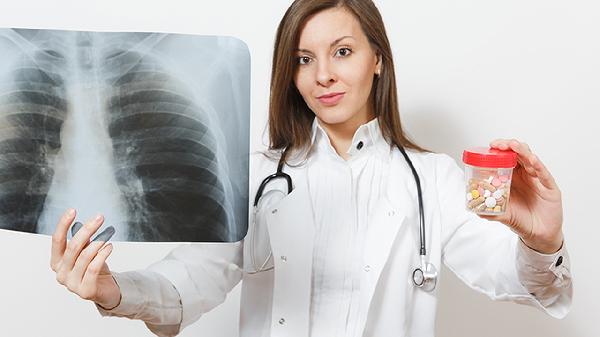

肺心病可能由慢性阻塞性肺疾病、肺动脉高压、睡眠呼吸暂停低通气综合征、肺结核、先天性心脏病等原因引起,可通过氧疗、药物治疗、手术治疗等方式干预。肺心病是肺部疾病导致心脏负荷增加的病理状态,需结合具体病因制定治疗方案。

长期吸烟或空气污染等因素引发慢性支气管炎和肺气肿,导致肺泡破坏和气道阻塞。肺部血管床减少使肺动脉压力升高,右心室为克服阻力代偿性肥厚,最终发展为肺心病。患者常伴有咳嗽、咳痰和活动后气促。治疗需使用沙美特罗替卡松粉吸入剂缓解气道痉挛,乙酰半胱氨酸颗粒促进排痰,并配合长期家庭氧疗。

结核分枝杆菌感染造成肺组织广泛纤维化,不仅减少有效呼吸面积,还会牵拉肺动脉形成机械性狭窄。病变累及超过两个肺叶时,右心后负荷明显增加。规范使用异烟肼片、利福平胶囊等抗结核药物可控制病情进展,合并大咯血时需行支气管动脉栓塞术。